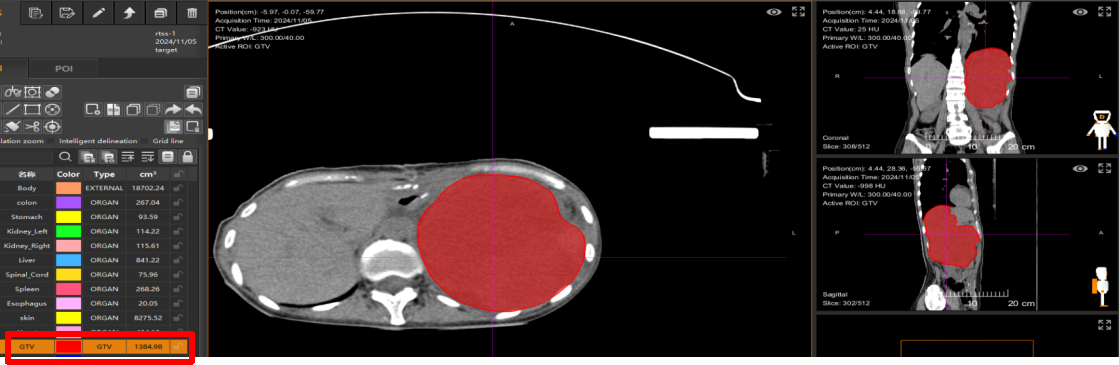

4. 重(碳)离子治疗与疗效 行重(碳)离子治疗局部根治性治疗。治疗前(2024年11月5日):CT显示腹腔内巨大肿瘤,肿瘤体积为1384.98 cm³。患者因疼痛无法弯腰,行走困难。治疗5次后(2024年11月21日):复查CT显示肿瘤明显缩小,肿瘤净体积缩小至558.89 cm³,体积缩小率为60%。临床症状改善:仅治疗2次后,患者腰背部疼痛即得到显著缓解,可正常行走。治疗结束时影像显示,与治疗前相比,肿瘤已被灭活,体积大幅缩小,并处于吸收消散过程中。

上图(上排):重(碳)离子治疗前(2024年11月5日)CT图像,红圈内示巨大腹腔复发肿瘤。上图(下排):重(碳)离子治疗5次后(2024年11月21日)CT图像,示肿瘤明显缩小。

转至武威重离子中心接受重(碳)离子治疗,2024年11月5日,重(碳)离子治疗计划,治疗前肿瘤体积:1384.98cm3。红色为肉瘤部分。

在武威重离子中心接受重(碳)离子治疗,治疗前肿瘤净体积:1384.98 cm3,治疗5次肿瘤净体积缩小为:558.89cm3,肿瘤体积缩小了60%。